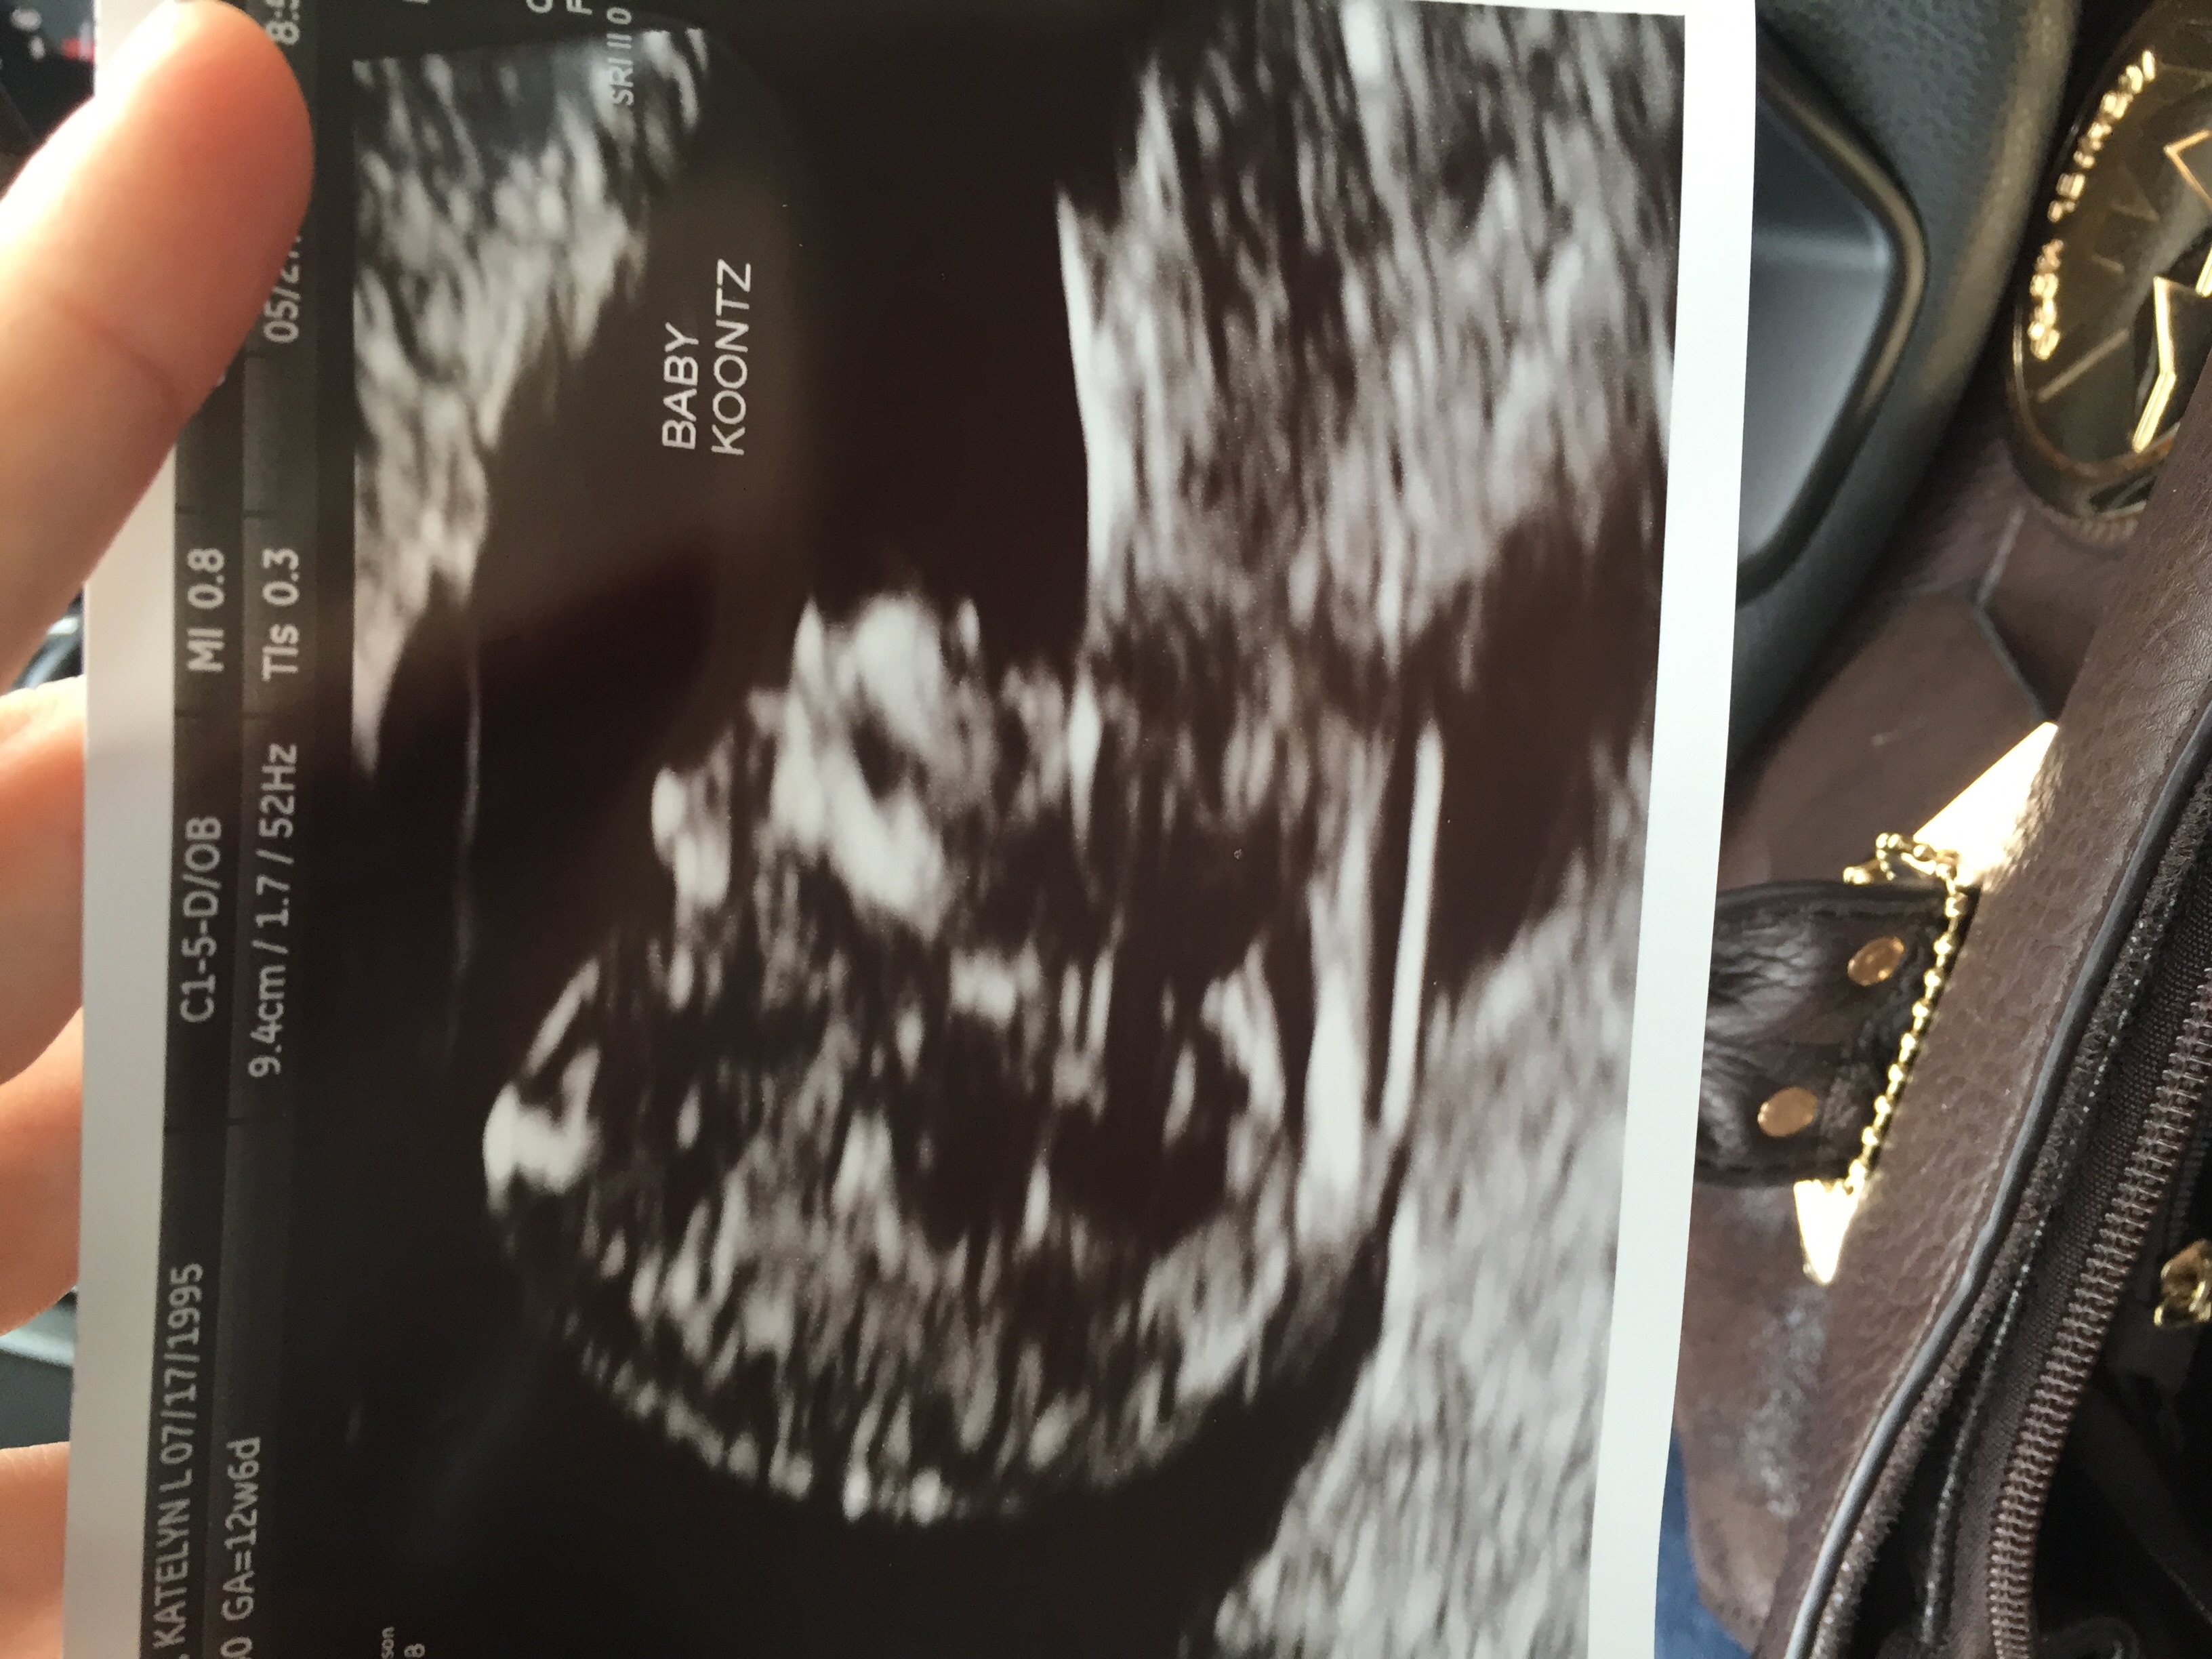

I already knew we were having a boy from the MaterniT21 blood test but we could clearly see the penis on today's ultrasound (12 weeks 3 days).

Anyway, the point of my post is that if any of you have a 12 week ultrasound coming up, and it's a boy, you may be able to see!

(Obviously quality of US machine, baby's position, uterine positioning, etc all come into play.)

I guarantee what you saw was this "nub".

There IS a "nub theory" some techs swear by. Depending on the angle of the nub (above 30 degrees means boy, I think) you can sometimes determine the gender but obviously it's not 100% accurate

According to the nub theory it does have an angle so we are probably having a boy.